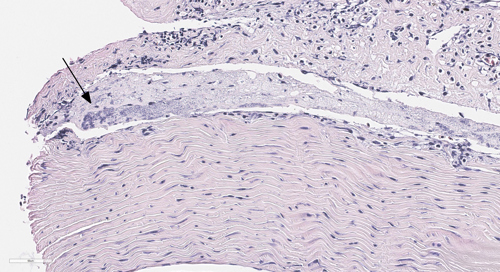

Bilde 2: Histologisk snitt. HE-farging. Bakterier og betennelsesceller (boks) i blodkar i hjerte, fra en sak med påvist Pseudomonas spp.

Pseudomonas spp. er vanlig forekommende bakterier, og de fleste infeksjoner blir oppfattet som opportunistiske infeksjoner som et resultat av dårlig vannkvalitet. I noen tilfeller kan imidlertid Pseudomonas fluorescens være hovedproblemet til økt dødelighet i settefiskanlegg. Gjennom vinteren har vi imidlertid sett flere tilfeller fra PO7 og 8 av hittil ukjente varianter av bakterien som har gitt systemisk infeksjon, og forårsaket dødelighet hos affisert laks i sjø.

Sykdomstegn hos laks med infeksjon med Pseudomonas spp. har vært utstående øyne, blødninger i øyne og svømmeblære, væske i hjertehule, fibrin på lever og lesjoner ved brystfinnebasis. Det har vært økt dødelighet forbundet med sykdomsutbruddene. Sykdommen har blitt håndtert med å ta ut enkeltmerder, samtidig som fiskegruppene i størst mulig grad har fått stå i ro. I tilfeller hvor det har vært behov for behandling, har det blitt valgt mest mulig skånsomme metoder.

Bakterieisolater fra utbruddene har blitt analysert med utvidet sekvensering, hvor flere gener har blitt undersøkt. Resultatene viser at isolatene fra PO7 er identiske med hverandre, men ikke like de som er blitt påvist fra PO8. Vi overvåker alle innsendelser hvor det er mistanke om Pseudomonas spp. for å følge situasjonen videre.